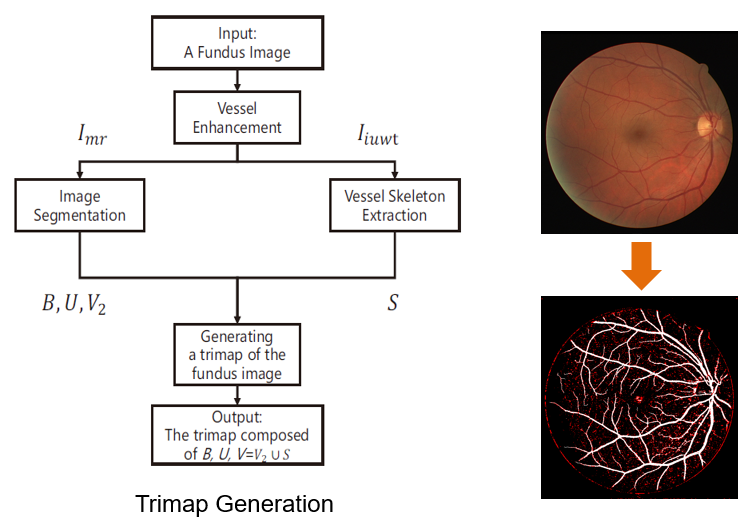

图一 基于分层抠图模型的血管分割算法总体流程 如图一所示,基于分层抠图模型的血管分割算法流程由三分图的生成(Trimap Generation)[4]和抠图(Matting)两步组成。在三分图生成中,为了提高血管的对比度,我们采用小波变换和形态学处理对血管的整体特征进行增强,然后结合阈值处理和血管的形状特征实现图像的分割和血管的主干部分提取,进而获得眼底图像的三分图。下面给出了三分图生成流程和实例展示,如图二所示。

图二 三分图的生成流程和实例展示 在抠图环节提出了分层抠图模型,实现三分图的进一步分割。下面给出了分层抠图模型的算法框架和实例展示,如图三所示。该算法主要分为两步: 对未知像素点的分层(Stratifying the unknown pixels)和分层更新(Hierarchical Update)。